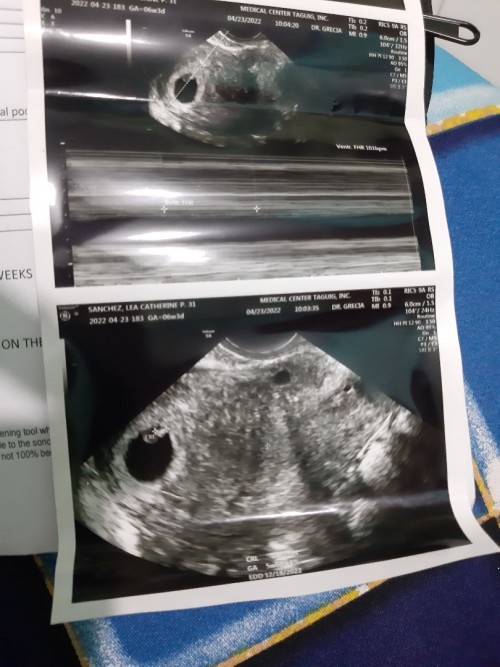

Ilang weeks nagpakita si baby sa trans v?

Hi mga mamsh, ilang weeks po kayo nung una nyo nakita si baby sa trans v? On saturday pa po kasi ako nakasched magpatrans v. As per tracker 6weeks & 3days plang po ako nun. May makikita na po kaya baby?? Share nyo naman kwento nyo mga mamsh kung ilang weeks una nagpakita si baby sa trans v. Thanks in advance. #advicepls

8 weeks mas sure 😊

7 weeks and 2 days

5weeks & 6days❤

sakin po 7 weeks

8weeks momsh

8weeks&2days

3 weeks 😇